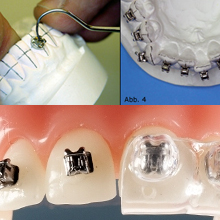

Mini-Brackets

/minibreakits.jpg) Die im Vergleich zu Standardbrackets geringere Größe der Minibrackets sieht im Mund nicht nur besser aus, sondern erhöht auch den Tragekomfort der festen Spange, Irritationen der Schleimhäute durch Ecken und Kanten sind seltener.

Die im Vergleich zu Standardbrackets geringere Größe der Minibrackets sieht im Mund nicht nur besser aus, sondern erhöht auch den Tragekomfort der festen Spange, Irritationen der Schleimhäute durch Ecken und Kanten sind seltener.

Reibungsarme SL-Brackets

Dies sind Brackets, bei denen auf Grund ihrer besonderen Konstruktion die Behandlungsbögen nicht mittels Ligaturen befestigt werden müssen. Wegen der dadurch erheblich verringerten Reibungskräfte bewegen sich die Zähne schneller und mit geringeren Kräften. Die Zahnbewegungen sind somit auch weniger schmerzhaft.

Dies sind Brackets, bei denen auf Grund ihrer besonderen Konstruktion die Behandlungsbögen nicht mittels Ligaturen befestigt werden müssen. Wegen der dadurch erheblich verringerten Reibungskräfte bewegen sich die Zähne schneller und mit geringeren Kräften. Die Zahnbewegungen sind somit auch weniger schmerzhaft.

Transparente Brackets

Transparente Brackets sind ästhetisch sehr vorteilhaft und lassen die feste Zahnspange im Vergleich zu herkömmlichen Metallbrackets wesentlich unauffälliger erscheinen. Die in unserer Praxis verwendeten Brackets sind von hoher, farbbeständiger Qualität und verfärben sich nicht während der Behandlung.

Transparente Brackets sind ästhetisch sehr vorteilhaft und lassen die feste Zahnspange im Vergleich zu herkömmlichen Metallbrackets wesentlich unauffälliger erscheinen. Die in unserer Praxis verwendeten Brackets sind von hoher, farbbeständiger Qualität und verfärben sich nicht während der Behandlung.

Lingualtechnik (inkognito – ist nicht in allen Fällen möglich!)

Wenn eine festsitzende Apparatur nötig ist und niemand etwas davon bemerken soll, ist Lingualtechnik die einzige Lösung! Hier wird die Apparatur auf der Innenseite der Zähne angebracht, sodass man von außen nur die Verbesserung der Zahnstellung, nicht aber die Zahnspange sieht. Allerdings ist dies auch die aufwändigste und damit teuerste Lösung, deren Kosten bislang von keiner Versicherung vollständig übernommen werden. Lingualtechnik ist auch nicht in allen Fällen sinnvoll bzw. möglich, lassen Sie sich dazu von uns beraten.

Wenn eine festsitzende Apparatur nötig ist und niemand etwas davon bemerken soll, ist Lingualtechnik die einzige Lösung! Hier wird die Apparatur auf der Innenseite der Zähne angebracht, sodass man von außen nur die Verbesserung der Zahnstellung, nicht aber die Zahnspange sieht. Allerdings ist dies auch die aufwändigste und damit teuerste Lösung, deren Kosten bislang von keiner Versicherung vollständig übernommen werden. Lingualtechnik ist auch nicht in allen Fällen sinnvoll bzw. möglich, lassen Sie sich dazu von uns beraten.

Indirekte Klebetechnik

Das indirekte Klebeverfahren wurde zur Verbesserung der Positionierungsgenauigkeit der Brackets und zur Verringerung der Unannehmlichkeiten für den Patienten eingeführt. Hierbei werden die Brackets reversibel auf die Situationsmodelle geklebt und in einem aufwändigen Verfahren individuelle Übertragungsschienen angefertigt. Dadurch erfolgt der Einbau der „festen Spange“ nicht nur mit maximaler Genauigkeit, sondern auch komfortabler und in wesentlich kürzerer Zeit für die Patienten.

Das indirekte Klebeverfahren wurde zur Verbesserung der Positionierungsgenauigkeit der Brackets und zur Verringerung der Unannehmlichkeiten für den Patienten eingeführt. Hierbei werden die Brackets reversibel auf die Situationsmodelle geklebt und in einem aufwändigen Verfahren individuelle Übertragungsschienen angefertigt. Dadurch erfolgt der Einbau der „festen Spange“ nicht nur mit maximaler Genauigkeit, sondern auch komfortabler und in wesentlich kürzerer Zeit für die Patienten.

Der wesentliche Vorteil dieser Methode liegt jedoch in einer deutlich kürzeren Behandlungszeit für die Patienten, da die festsitzende Spange auf Grund der höheren Genauigkeit der Bracketpositionen wesentlich früher wieder abgenommen werden kann.